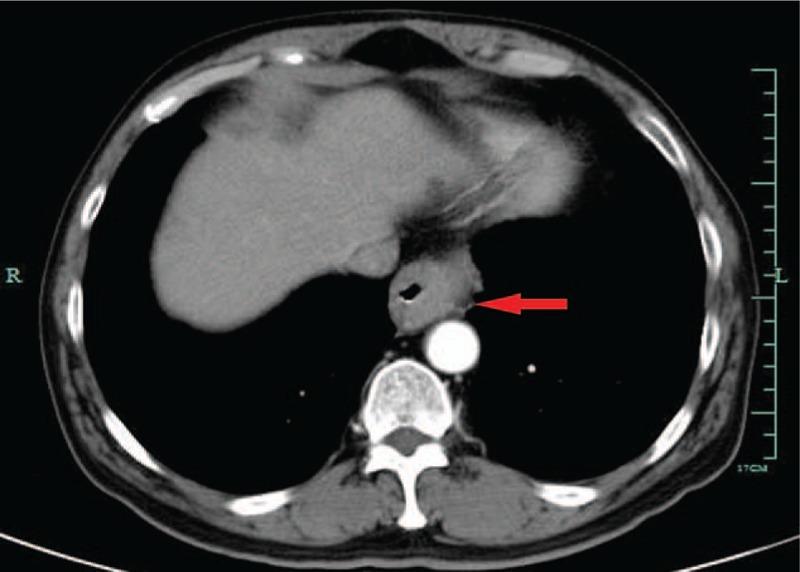

In this case report, we describe a case of a 59-year-old man who presented with difficulty in swallowing. Iohexol swallowing revealed a malignant-appearing structure in the inferior-thoracic region.

Biopsy of the lesion under endoscopy demonstrated a mucoepidermoid carcinoma of the esophagus.

在本病例报告中,我们描述了一名59岁男性患者,他出现吞咽困难。碘海醇吞咽检查显示胸段下部有一个疑似恶性的结构。

内镜下病变活检显示为食管黏液表皮样癌。